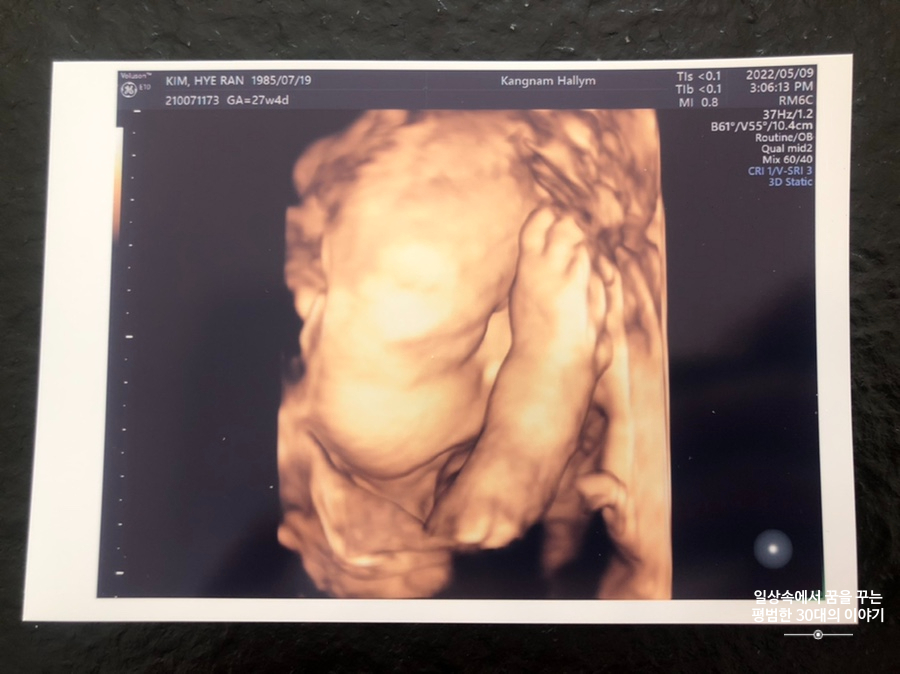

오늘은 입체 초음파 보는 날!!! 입체 초음파는 처음인데다 3주 만에 이안이 얼굴을 본다 생각하니 무척 설레는 마음으로 병원에 갔다. 첫 번째 시도에서는 계속 내 등 쪽으로 얼굴을 대고 엎드려 있어 실패! 초코우유 먹고 열심히 걸은 후, 30분 뒤에 다시 진행한 두 번째 시도에서는 얼굴 반쪽을 보여줬다. 얼굴 전면을 보지 못해 너무 아쉬웠지만 그래도 손가락 빨고 있는 모습, 웃고 있는 모습, 입 뻐끔 거리는 모습, 발차기 하는 모습, 손가락 쥐었다 폈다 하는 모습, 손을 휘적휘적 거리는 모습 등 다양한 모습을 보여줘서 그것만으로도 충분히 만족스러웠다. 내가 다니고 있는 강남성심병원은 입체 초음파가 다른 병원에 비해 무척 비싼 편인데(진료비 내역을 보니 초음파 진단료가 129800원 나옴) 그나마 위안을 삼을 수 있는 것은 화질이 그나마 좋은 편이라는 것이다.